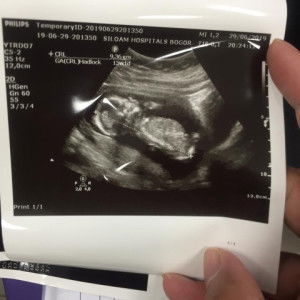

Aku dr awal hamil sampe skrg 17week lebih ga pernah sekalipun minum susu hamil Bun .. Yg penting rajin minum vitamin, buah, sayuran, makanan yg bergizi lainnya pun udah cukup .. Susu mah ga wajib . Alhamdulillah setiap USG semuanya sehat dan normal 😊